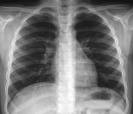

Hitam-putih (radiolusen-radioopak) sebuah foto Rontgen [selanjutnya ditulis foto saja] tergantung pada daya tembus sinar X pada suatu benda. Benda-benda yang mudah ditembus sinar X akan memberikan gambaran hitam (radiolusen). Benda-benda yang sukar ditembus sinar X akan memberikan gambaran putih (radioopak). Ada juga bayangan tidak terlalu hitam (moderately radioluscent) dan bayangan tidak terlalu putih (moderately radioopaque). Diantara radiolusen sedang dan radioopak sedang ada bayangan keputih-putihan (intermediate).

Tidak semua foto layak baca. Misalnya pada foto Rontgen Thorax, foto dikatakan layak baca,salah satu syaratnya, bila memenuhi kualitas hitam-putih tertentu yang bergantung pada:

> Tegangan. Mempengaruhi daya tembus sinar X. Bila KV cukup, maka corpus vertebra thorax III harus terlihat, yang semakin ke bawah semakin tidak jelas.

> Mempengaruhi jumlah sinar X yang dikeluarkan. Mempengaruhi kontras pada film. Cara mengetahui cukup atau tidaknya yaitu dengan menyimpan jari di belakang pinggir foto yang warnanya paling hitam. Normal -> jari tetap terlihat. Abnormal-> terlalu hitam (keras) atau terlalu putih (lunak)